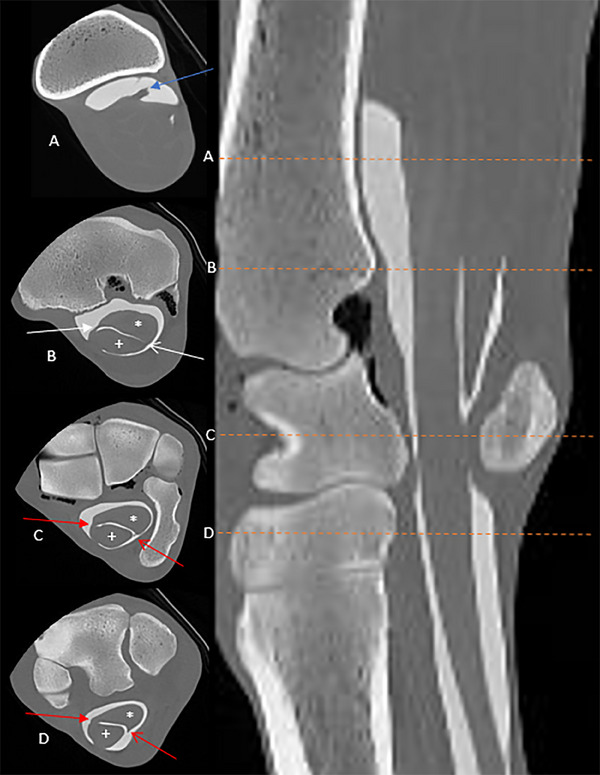

Exploratory tenoscopy is considered the gold standard technique to identify intrathecal pathology of the equine carpal flexor tendon sheath (CFTS). Preoperative diagnosis allows for more precise prognostication and surgical planning, potentially associated with improved surgical outcomes. This prospective, descriptive, anatomical study aimed to describe the anatomy of the equine CFTS using noncontrast and contrast CT in clinically normal cadaver limbs. Ten pairs of equine forelimbs free of gross external abnormalities were examined from mid-antebrachium to distal metacarpus. Specimens initially underwent noncontrast CT examination using 135 kVp, dynamic mAs, and 1 mm slice thickness. Contrast media (iohexol) diluted in saline (total 60 mL, final concentration 75 mg/mL) was injected into the CFTS from a lateral approach before the CT examination was repeated. Tenoscopy was then performed using the conventional lateral approach. Dissection was used to compare the gross, tenoscopic, and imaging findings. The combined noncontrast CT and contrast CT examinations provided excellent anatomical detail of intrathecal and extrathecal structures. Detailed anatomy of the previously undescribed proximal mesotenon and manica of the common mesotenon were also identified. The distal termination of the CFTS was beyond the mid-metacarpus in most specimens, which is significantly more distal than previously reported. This is an important consideration when administering local anesthesia in orthopedic examinations to prevent potential iatrogenic CFTS penetration, which may induce sepsis if the aseptic technique is not followed. Noncontrast and contrast CT can be used to accurately identify CFTS anatomy. Documentation of new intrathecal structures provides a greater understanding of CFTS anatomy.